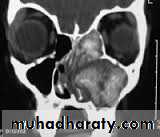

Investigation

4. CT- scan of the sinuses may show

microcalcification of opaque fungal mass in the

non-invasive form due to accumulated heavy

metals, e.g. calcium, manganese. There may be

evidence of bone expansion. The invasive type,

however, will show evidence of bone destruction

with spread of disease outside the sinuses. MRI

scanning may further help delineate fungal mucin

from reactive inflammation .